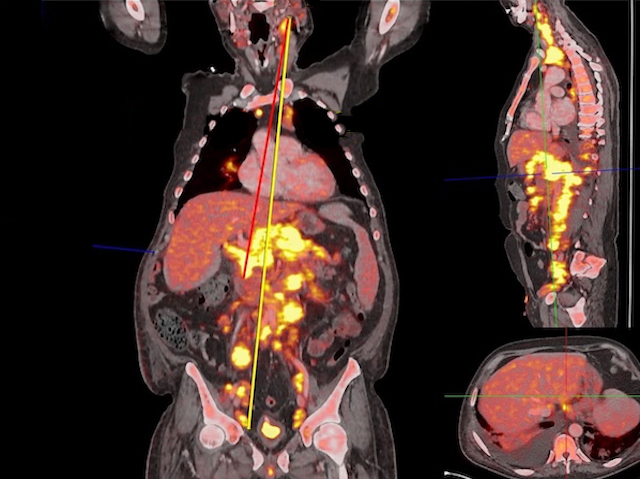

El mesurament de la major distància entre dos tumors (Dmax) en el cos d'un pacient amb càncer, obtinguda mitjançant tomografies computades, s'utilitza com a marcador de pronòstic (un indicador de la progressió de la malaltia i de l'esperança de vida del pacient) en les teràpies oncològiques convencionals, però no s'ha estudiat en profunditat en el context de la cada vegada més prometedora teràpia CAR-T (un tipus d'immunoteràpia en la qual es reprograma el propi sistema immunitari del pacient perquè ataque el seu tumor). En este estudi, després de realitzar este mesurament en 39 pacients abans i després de la teràpia CAR-T per al limfoma (un tipus de càncer dels glòbuls blancs), es va observar que el càncer progressava més ràpidament en aquells amb un Dmax elevat, però això no predeia la seua supervivència global.

Department of Radiology, University Hospital, LMU Munich, Munich, Alemanya